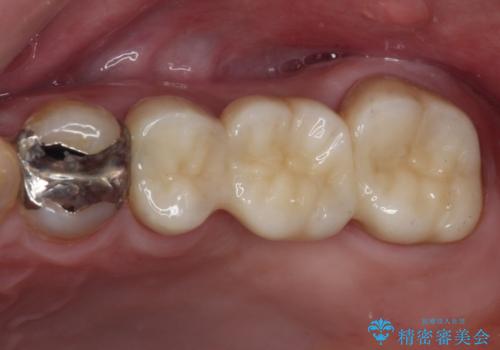

前後の歯は銀歯が装着されていたため、ブリッジによる補綴治療として、前後の歯もセラミックに置き換えることとしました。

歯根のみとなっていた上顎の歯は、そのうち治療すれば残せるであろうと思っていたようですが、どこの歯医者に相談しても抜歯と言われたため、抜歯することとしたようです。

むし歯は放置して改善することはあり得ませんので、早めの処置が大切です。